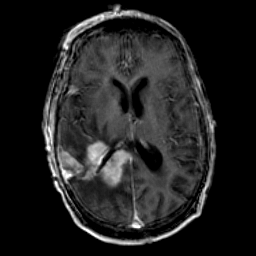

Glioma Overlay -- Slice #11

[Home][Help][Clinical] Slice 11